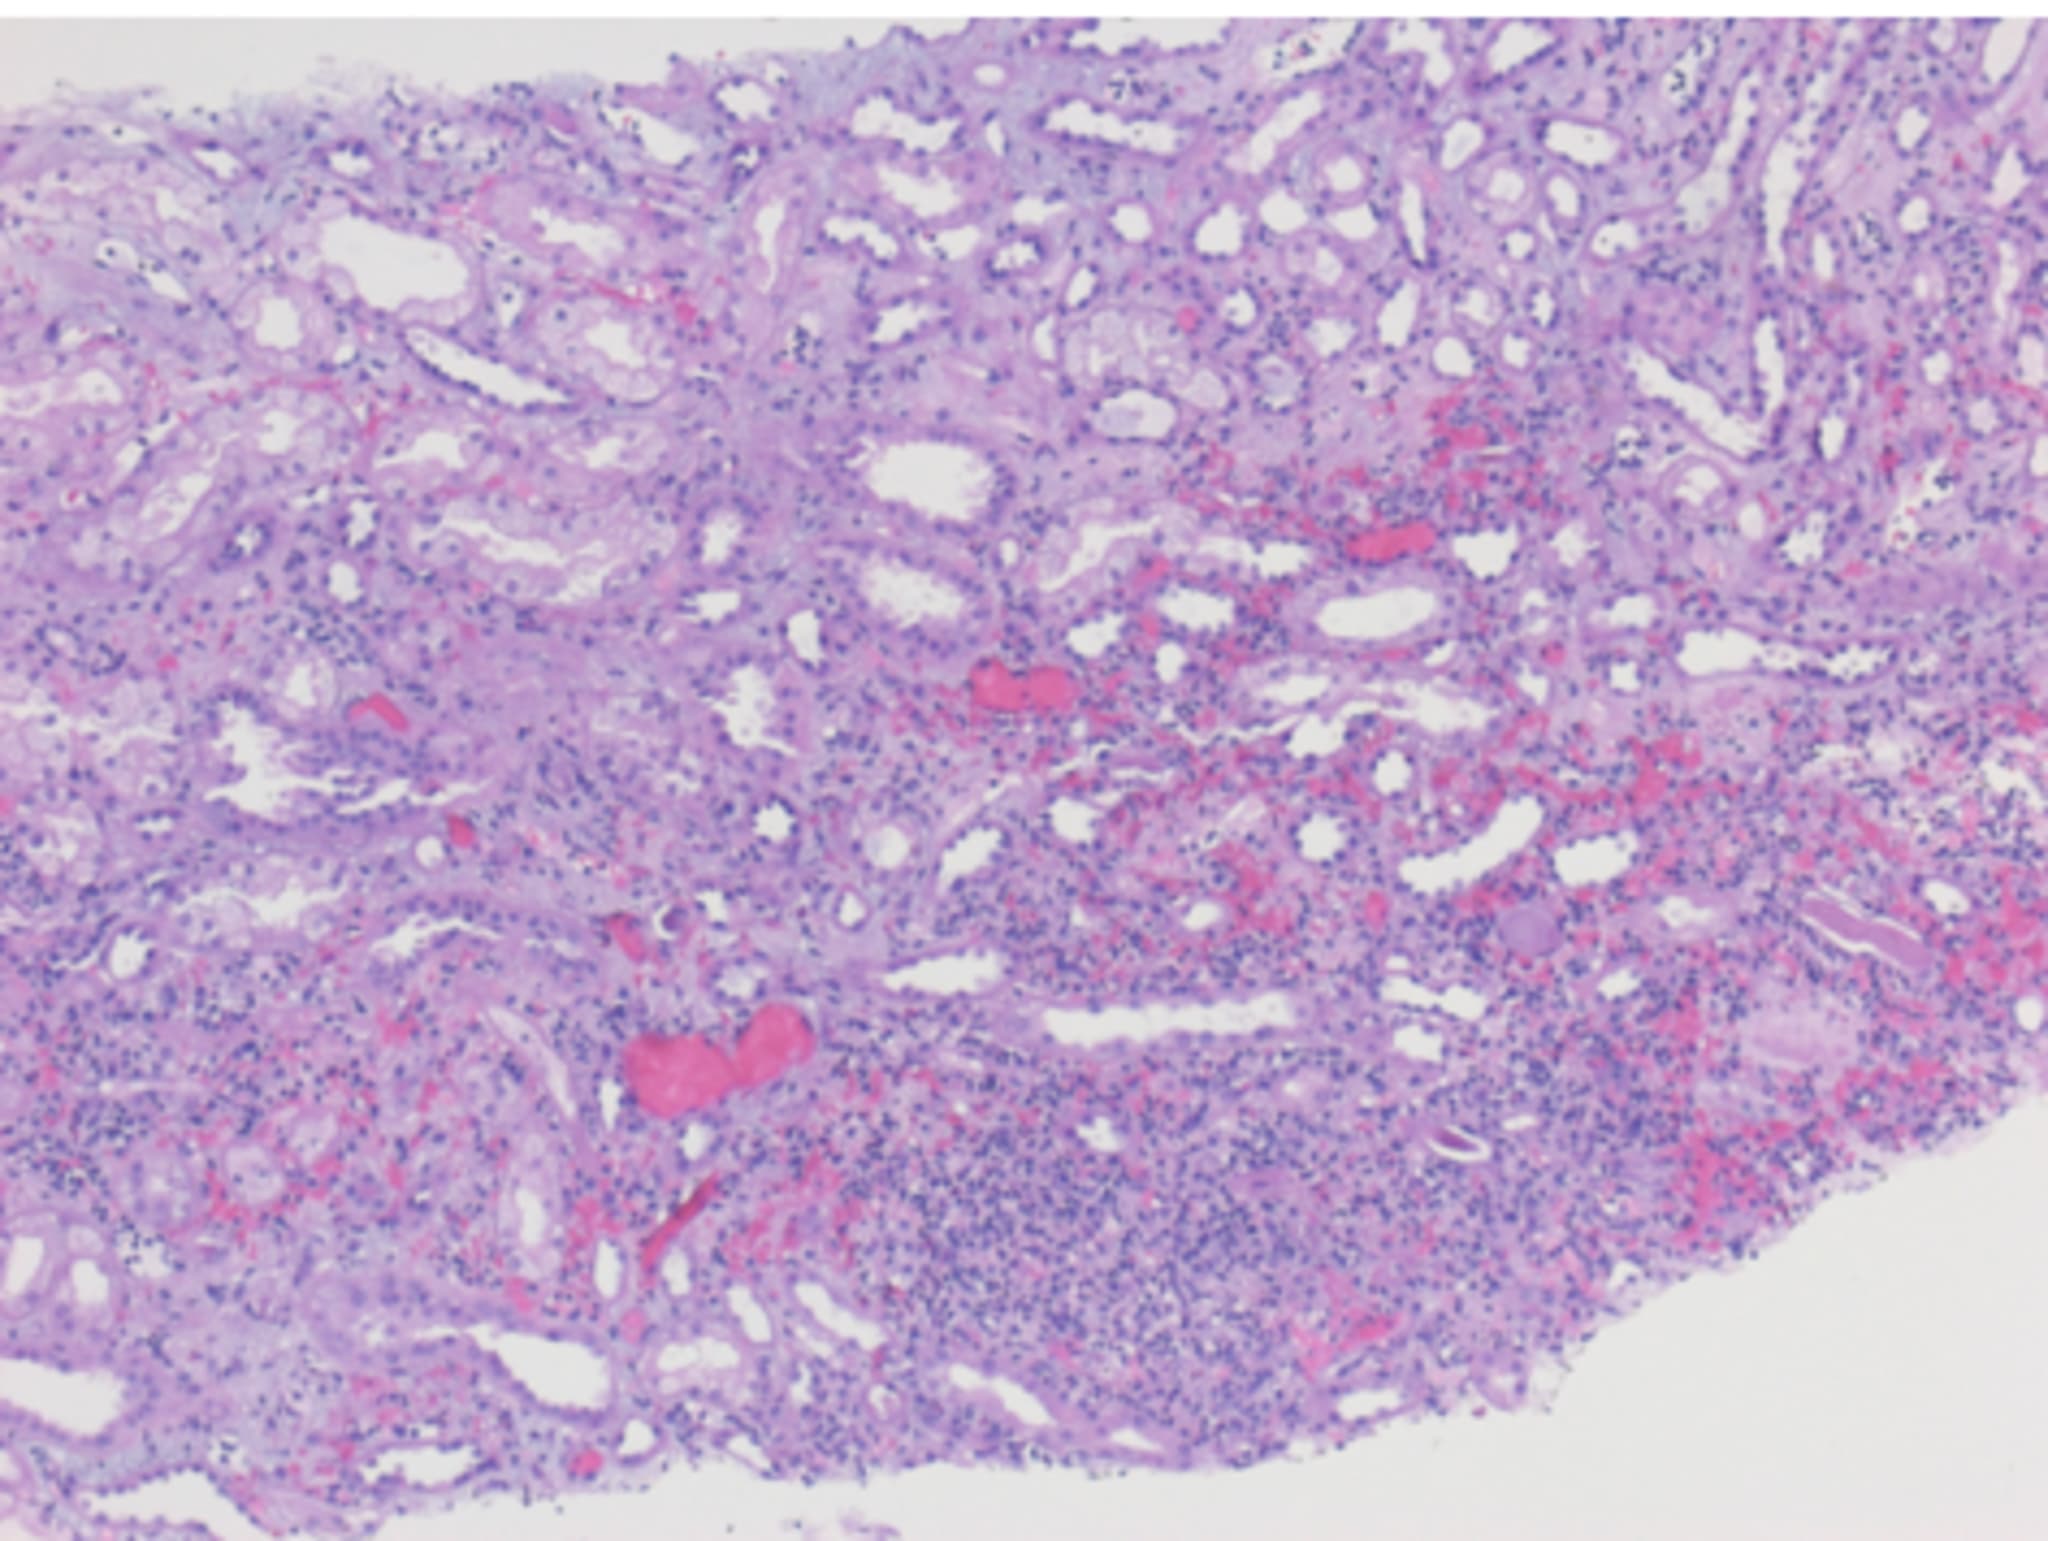

Schließlich liegen die Ergebnisse der Nierenbiopsie vor und bringen die entscheidenden Hinweise:

Intrakapillär proliferative und angedeutet auch exsudative Immunkomplex-Glomerulonephritis, a.e. Nierenbeteiligung bei IgA Vaskulitis mit zusätzlich a.e. infekt-assoziierter glomerulärer Nephropathie (GN)